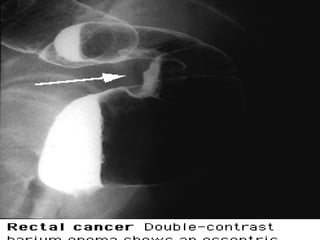

Neoplasia

• El cáncer de colon es una causa menos común de

hematoquezia, pero es causa de sangrado en 60%

pacientes > 50 años.

• Raro en pacientes mas jóvenes.

• Sangrado tiende a ser recurrente y leve.

• Sangrado rojo y brillante: lesiones del lado izquier-

do y las del lado derecho son de rojo vinoso o color

marrón ; mas raramente melena.

• 20% presenta metástasis al momento de hacer el

diagnóstico

Neoplasia • El cáncerde colon es una causa menos común de hematoquezia, pero es causa de sangrado en 60% pacientes > 50 años. • Raro en pacientes mas jóvenes. • Sangrado tiende a ser recurrente y leve. • Sangrado rojo y brillante: lesiones del lado izquier- do y las del lado derecho son de rojo vinoso o color marrón ; mas raramente melena. • 20% presenta metástasis al momento de hacer el diagnóstico